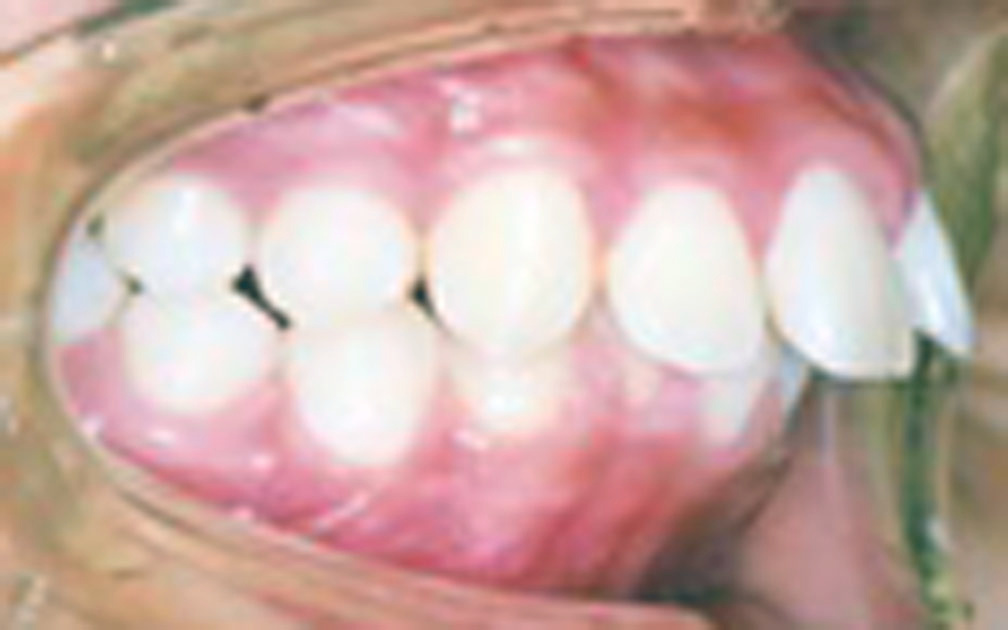

矯正の症例1 (診断名)上顎前突(ジョウガクゼントツ)

矯正の症例2 (診断名)下顎前突(カガクゼントツ)

(患者様の主訴)受け口が気になる

(治療開始年齢)7歳11カ月

(主な治療装置)リンガルアーチ

(抜歯部位)非抜歯

(治療期間)5カ月

(治療費)¥290000

(個別リスク・副作用)上顎前歯部を前方(唇側)に傾斜させるため、下顎の前歯部からの突き上げがあり、歯根が吸収するリスクがあります。

思春期性成長のためにまた反対咬合になる可能性があります。そのため長期にわたり成長を観察する必要があります